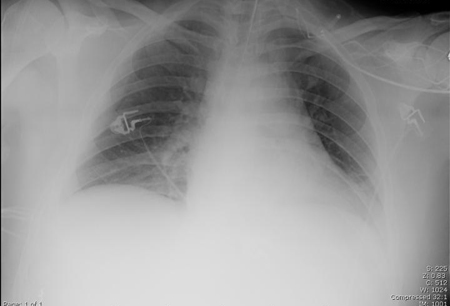

Chest x-ray

A chest x-ray should be obtained early in the evaluation of chronic cough.[38] Although it is not diagnostic of the most common causes, findings may quickly divert the evaluation to causes of greater gravity, such as structural lung diseases. These include lung cancer, pulmonary fibrosis, tuberculosis, bronchiectasis, pneumonia, aspiration, and sarcoidosis.[Figure caption and citation for the preceding image starts]: Chest x-ray showing hyperinflation in a patient with COPD. The hyperinflation is caused by the emphysema component of COPD, rather than the chronic bronchitis that underlies symptoms of coughFrom the personal collection of Dr M. A. Sharifabadand, SUNY at Stony Brook School of Medicine, Department of Pulmonary and Critical Care Medicine, Mineola, New York and Dr J. P. Parsons, The Ohio State University Medical Center, Columbus; used with permission [Citation ends].com.bmj.content.model.assessment.Caption@65a65855[Figure caption and citation for the preceding image starts]: Chest x-ray showing multiple miliary lung metastases (arrows). The primary tumour was a thyroid carcinomaE. Dick, Student BMJ. 2001;9:10-12 [Citation ends].com.bmj.content.model.assessment.Caption@25657fee[Figure caption and citation for the preceding image starts]: Chest x-ray showing left hilar carcinoma (arrow)From: E. Dick, Student BMJ. 2000;8:358-360 [Citation ends].com.bmj.content.model.assessment.Caption@567b9fef[Figure caption and citation for the preceding image starts]: Chest x-ray showing a cavitating right hilar carcinoma (arrow)E. Dick, Student BMJ. 2001;9:10-12 [Citation ends].com.bmj.content.model.assessment.Caption@3d6fa55[Figure caption and citation for the preceding image starts]: Chest x-ray in a patient with bronchogenic carcinoma showing a left-sided pleural effusionFrom: R. Thakkar, Student BMJ. 2001;9:458 [Citation ends].com.bmj.content.model.assessment.Caption@5b46acec[Figure caption and citation for the preceding image starts]: Chest x-ray showing interstitial fibrosis in a patient with amiodarone pulmonary toxicityFrom the personal collection of Dr A. Pataka and Professor P. Argyropoulou, Aristotle University, Thessaloniki, Greece; used with permission [Citation ends].com.bmj.content.model.assessment.Caption@2c3c94b0[Figure caption and citation for the preceding image starts]: Chest x-ray showing pulmonary tuberculosis with cavitationFrom the personal collection of Dr M. Narita, Department of Pulmonary and Critical Care Medicine, University of Washington [Citation ends].com.bmj.content.model.assessment.Caption@3dd7f84b[Figure caption and citation for the preceding image starts]: Chest x-ray showing multiple discrete nodules throughout both lungs (one of which is circled) in a patient with miliary tuberculosisE. Dick, Student BMJ. 2001;9:10-12 [Citation ends].com.bmj.content.model.assessment.Caption@23fa6365[Figure caption and citation for the preceding image starts]: Chest x-ray with lack of normal tapering producing a tram line in a patient with bronchiectasisFrom the personal collection of Dr S.M. Bhorade, University of Chicago Medical Center; used with permission [Citation ends].com.bmj.content.model.assessment.Caption@36b415f2[Figure caption and citation for the preceding image starts]: Chest x-ray with dilated and thickened airways in a patient with bronchiectasisFrom the personal collection of Dr S.M. Bhorade, University of Chicago Medical Center; used with permission [Citation ends].com.bmj.content.model.assessment.Caption@78e208fa[Figure caption and citation for the preceding image starts]: Chest x-ray showing increased opacification of the right perihilar region and superior segment of the right lower and upper lobes consistent with worsening aspiration pneumoniaFrom the personal collection of Dr R. Kanner, University of Utah School of Medicine [Citation ends].com.bmj.content.model.assessment.Caption@71be2c1f[Figure caption and citation for the preceding image starts]: Portable chest x-ray with bibasilar opacities, worse on the right than the left, in a patient with hospital-acquired pneumoniaFrom the personal collection of Dr F. W. Arnold, Division of Infectious Diseases, Department of Medicine, University of Louisville School of Medicine [Citation ends].com.bmj.content.model.assessment.Caption@2c704497[Figure caption and citation for the preceding image starts]: Chest x-ray showing early ill-defined opacities of the right upper lobe above the minor fissure consistent with early changes of aspiration pneumoniaFrom the personal collection of Dr R. Kanner, University of Utah School of Medicine [Citation ends].com.bmj.content.model.assessment.Caption@23fa54d0[Figure caption and citation for the preceding image starts]: A. Portable upright chest x-ray before aspiration; B. Chest x-ray 1 hour after aspiration, showing bilateral diffuse alveolar infiltrates, worse at the bases on the right sideFrom the personal collection of Dr S. Murgu and Dr H. Colt, University of California at Irvine Medical Center [Citation ends].com.bmj.content.model.assessment.Caption@7860be3a[Figure caption and citation for the preceding image starts]: Chest x-ray showing bilateral hilar adenopathy in a patient with sarcoidosisFrom the personal collection of Dr M.P. Muthiah, Division of Pulmonary and Critical Care and Sleep Medicine, University of Tennessee [Citation ends].com.bmj.content.model.assessment.Caption@31e94b4e